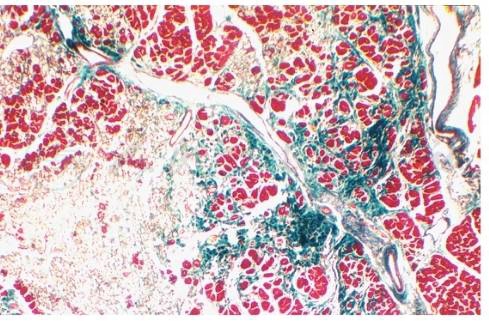

心肌损害成批发生,可以新旧并存(图3)。在心脏旧、新病变发生顺序通常是先左室、后右室,由内层向外层。在同一部位常见陈旧病变在中心,新鲜坏死在周边。北方地区的成人克山病这种新旧并存的现象相当多见,南方小儿亚急型病变多为一致性。坏死灶与冠状动脉走行密切相关,常见的有两种围血管坏死灶分布。

图3慢型克山病光镜下观察

(心肌坏死、瘢痕病灶、新旧病变并存)